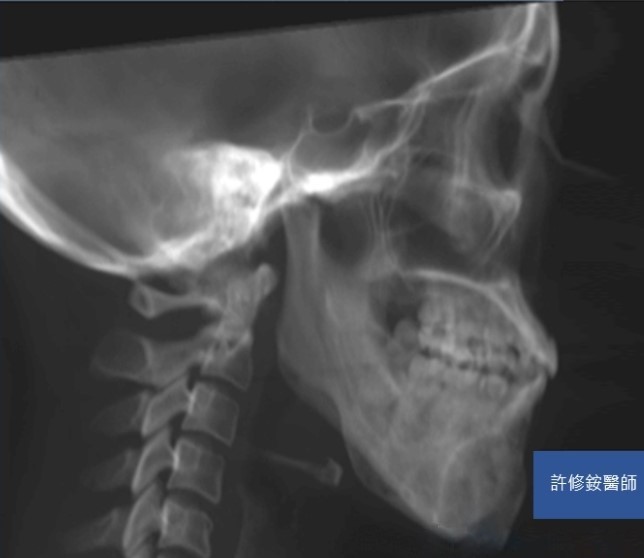

削骨手術需要精密的診斷與計算,加上顏面骨骼有特殊的圓弧與角度,精確的影像是基本要求。3D影像可協助醫師能檢視不同的切面,且影像重組後,專科醫師可自由旋轉影像由各種不同的角度檢視骨骼的變異,除了能完整地檢視病人的顏面骨並精準的訂定治療計劃;客人也能在手術前,藉由3D影像的模擬更理解醫師的解釋內容。

正顎、削骨手術需要精密的診斷與計算,加上顏面骨骼有特殊的圓弧與角度,精確的影像是基本要求。感謝科技進步,3D影像使醫師能檢視不同的切面,且影像重組後,醫師可自由旋轉影像由各種不同的角度檢視骨骼的變異。因此,醫師能完整地檢視病人的顏面骨並精準的訂定治療計劃。病人也能藉由3D影像的模擬更理解醫師的解釋內容。